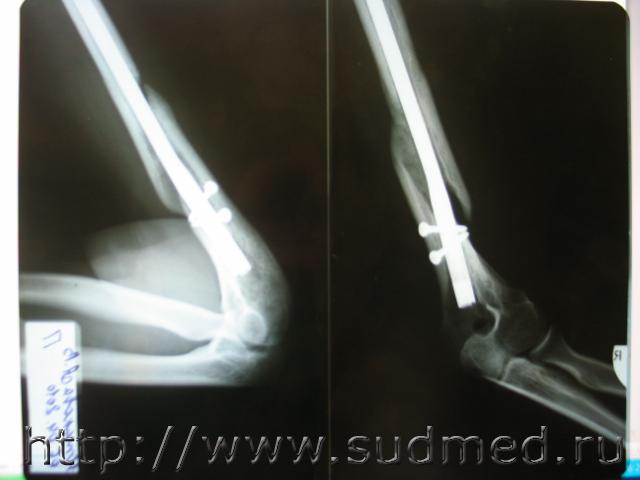

Нужна помощь в определении механизма перелома.

Экспертиза живого лица, дополнительная. Вопрос эксперту: возможность причинения перелома при падении из вертикального положения. Показания:

Проект выводов: 1. Винтообразная форма линии перелома - деформация кручения плеча вокруг своей оси, возможно при обстоятельствах указанных потерпевшим. Причинение перелома при падении из вертикального положения не характерно, в том числе при обстоятельствах, отраженных в протоколе следственного эксперимента.

Фото рентгенограмм прилагаю.

1. Винтообразный перелом плеча как раз характерен для падения из вертикального положения с упором на ладонь выпрямленной руки. Без этих дух условий - упор на ладонь с осевой нагрузнкой на плечо и выпрямленная рука, образование винтообразного перелома невозможно.

2. Судя по приведенной фотографии оба ключевых момента отсутствуют, что позволяет категорически исключить возможность образование винтообразного перелома при таком падении.

3. Образование такого перелома возможно, в том числе и при ударе по лотевому суставу или нижней трети плеча заведенной за спину руки - при этом заведение руки за спину создает вращательно сдвиговые напряжения в плечевой кости, а дополнительное поперечное воздействие в область перелома или вблизи него, выполняет роль дополнительного нагружения, после которого и может образоваться винтообразный перелом.

Я бы дал название перелому: винтообразно сгибательный (зубовидный край отломка) (диссертации после 2000 года Кислова М., Леоновой Е.).

Топики иногда читают и после закрытия обсуждения. На снимке реально очень красивый перелом, вот я и решил внести свою лепту.